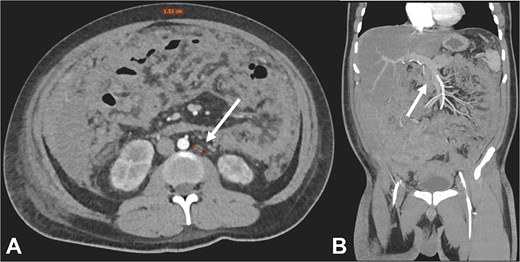

Contrast-enhanced CT in the venous phase: Axial view (A) and coronal reconstruction (B) demonstrated nodular thickening of the peritoneum with vascular enhancement, peritoneal implants measuring up to 6 mm (arrow), and plaque-like implants along the splenic margin (head arrow).

Contrast-enhanced CT in the arterial phase: Axial view (A) and coronal reconstruction (B) demonstrated mesenteric lymphadenopathy measuring up to 1.53 cm (white arrows).